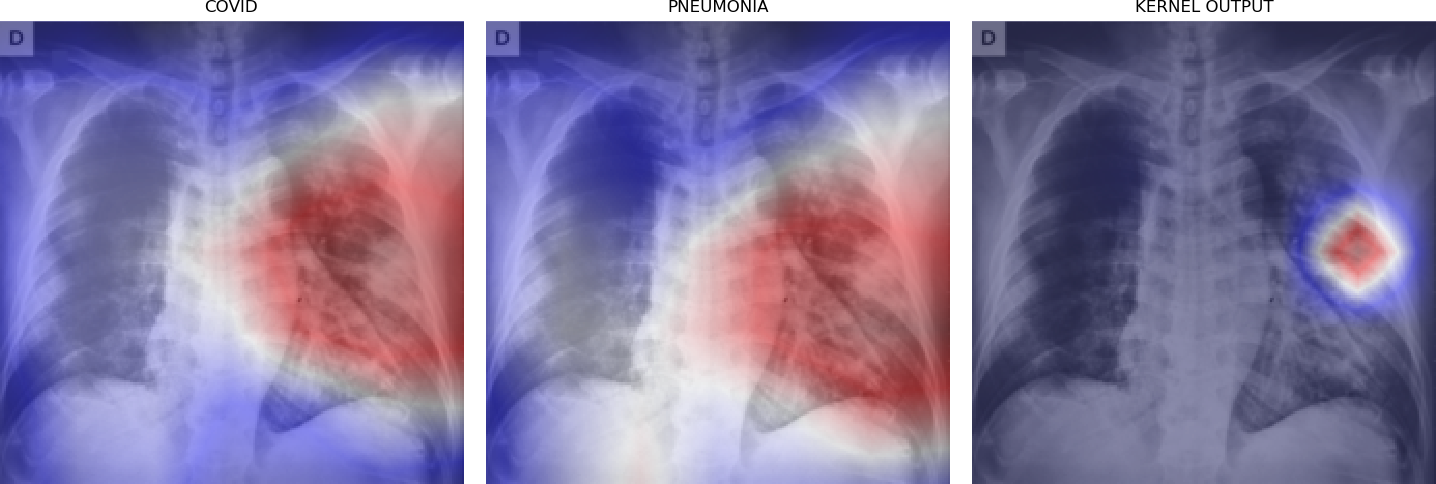

Figure 5 shows triples of X-ray images with superimposed class activation maps for predictions obtained from expert binary models (images one and two) with the third image showing the heat maps computed using our kernel. The intended use of our method is to examine positive classifications from two possibly overlapping classes (i.e. COVID-19, Pneumonia) and extract discriminative features pertaining to the class of interest, i.e. COVID-19. Triples (a)-(f) show positive classifications of COVID-19 and Pneumonia by their respective binary expert models along with class activation maps that localize the image region responsible for that classification. The third image in each triple shows a better localized image region for COVID-19 as computed using our method. Our method is intended to improve explainability of predictions under circumstances where both models return positive classifications resulting in significant overlap in activation maps.

Figure 6 demonstrates the role of the kernel parameter . It controls amplification of the directed differences among the activation maps. Higher values of concentrate the resulting heat map to a smaller region.